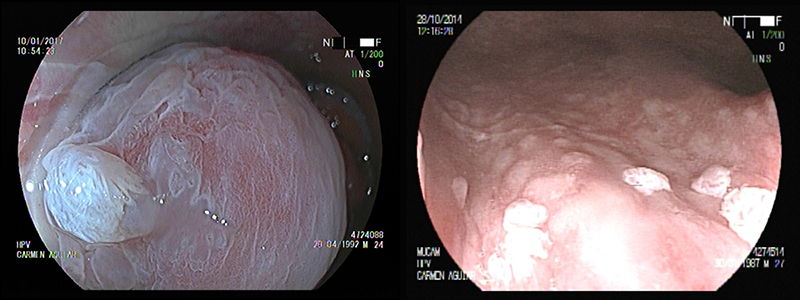

Endoscopía de Alta Resolución

y Análisis Histológico de las Biopsias

Se realiza con un endoscopio que se introduce en el canal anal y el recto. Se tiñe y magnifica la imagen hasta 100 veces su tamaño real. Se ponen en evidencia lesiones internas de muy pequeño tamaño imposibles de observar en una fibroscopía común. Se toman muestras biópsicas de las lesiones y se envían a un laboratorio de Anatomía Patológica con patólogos entrenados en esta patología.

Las muestras no superan los 3 mm y la toma es indolora. Con este procedimiento es posible explorar el canal anal y el recto, lo que posibilita diagnosticar lesiones que pueden asentar por encima del canal anal y pasan desapercibidas en una anoscopía.

El análisis histológico de estas muestras se realiza en el laboratorio de Anatomía Patológica y Citología Dra Carmen Álvarez Santin. El reconocimiento de la comunidad médica a la trayectoria de esta médica anatomopatóloga, le ha valido el nombramiento como miembro de la Academia Nacional de Medicina del Uruguay así como varios reconocimientos a nivel internacional. Junto con la Dra Ma.Carmen Rodríguez Álvarez especialista en dermopatología, forman parte de nuestro equipo médico desde el año 2013. El análisis de las muestras biópsicas confirmará la existencia y la benignidad o malignidad de la lesión.